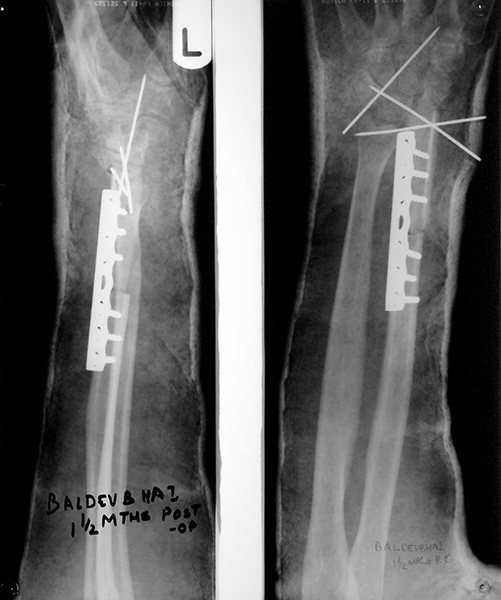

Case:5 Ewing sarcoma with implant failure

Breakage of Nail

Refixation with Angle Bladed Plate and Sever Graft

Ewing's Post Nailing and Bone Grafting

3 Months Post -Op

6 Months Post-Op